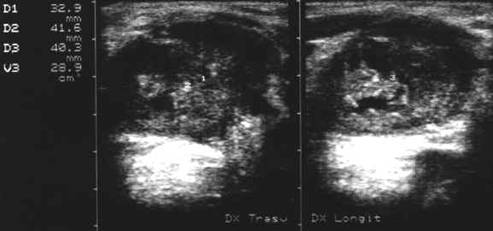

Lobul drept, proiectie trasversala si longitudinala.

Femeie de 29 ani. Nodul de consistenta dura in lobul

drept si istm.

Ecografia: nodul cu margini difuze in lobul drept si istm, care deformeaza

conturul anterior al glandei, structura parenchimatoasa, neoomogena, hipoecogena.

Prezenta de linfonoduli laterocervicali.

Citoaspiratia: carcinom papilar.

Examen histologic: carcinom papilar plurifocale varianta foliculara.